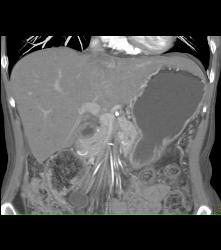

Antral Carcinoma